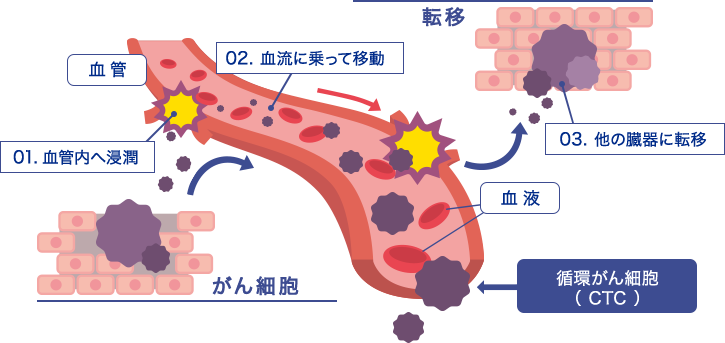

CTCとは何でしょうか?

がん細胞は周りの正常な組織を破壊しながら広がっていく(浸潤する)という特徴があります。この悪性の腫瘍が、がんです。時間とともに、悪性の腫瘍(がん)は、血管やリンパ管に入り、その流れにのって、ほかの臓器へと移動し、そこでもかたまりをつくるようになります。これががんの転移です。

その血液を流れているがん細胞をCTC(循環腫瘍細胞)と言います。

下図の紫色のものが、そのCTCになります。

なぜがん細胞は血液中に流れるのでしょうか?

がんは周りにある組織の血管に働きかけて新しい血管を作らせ、そこから成長するための酵素や栄養を獲得し大きくなります。がん細胞が成長するためには血管とつながる必要があり、結果として血液中にがん細胞が流れるのです。